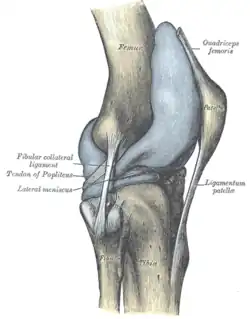

La rótula[1] (patella) es un hueso sesamoideo situado en el plano anterior de la articulación de la rodilla, engastada en el tendón del cuádriceps. Es aplanada, de forma triangular con vértice inferior, y su eje mayor mide unos 5 cm. El borde superior (base) y la cara anterior reciben las fibras del tendón del cuádriceps, y de su vértice parte el ligamento rotuliano que continúa al tendón del cuádriceps. La cara posterior (cara articular) posee la superficie articular para el fémur y, por debajo, una zona rugosa relacionada con formaciones adiposas de la articulación de la rodilla. La superficie articular consta de dos vertientes laterales separadas por una cresta roma central que se adaptan a la superficie rotuliana del fémur. Se considera el hueso sesamoideo más grande del cuerpo humano.

Las cuatro cabezas del cuádriceps (M. vasto intermedio, M. vasto lateral, M. vasto medial, M. recto femoral) se condensan en láminas tendinosas que confluyen en la proximidad de la rótula formando el tendón del cuádriceps, en cuyo espesor se localiza la rótula. El mayor componente de fibras emerge por el vértice inferior de la rótula y forma una potente cinta tendinosa denominada ligamento rotuliano que se inserta en la tuberosidad de la tibia.

Del sector inferior de los bordes laterales de la rótula emergen láminas fibrosas, las cuales contribuyen a reforzar la articulación de la rodilla. Un aspecto de interés es que los componentes tendinosos fibrilares de cada vientre del cuádriceps ocupan planos diferentes y pueden ser identificados en la región rotuliana. Las fibras del recto femoral, son las más superficiales y algunas de ellas saltan hasta el ligamento rotuliano sin insertarse en la rótula. Las fibras de los vasto medial y vasto lateral y ocupan un plano más profundo y, como se ha descrito antes, parte de sus componentes emergen por los bordes laterales de la rótula para reforzar la articulación de la rodilla. Las fibras más profundas son las del vasto intermedio, que se agotan en el borde superior de la rótula. Por encima de la rótula puede aparecer una bolsa sinovial interpuesta entre los planos tendinosos superficial y profundo del tendón del cuádriceps (bolsa subtendinosa prerrotuliana).